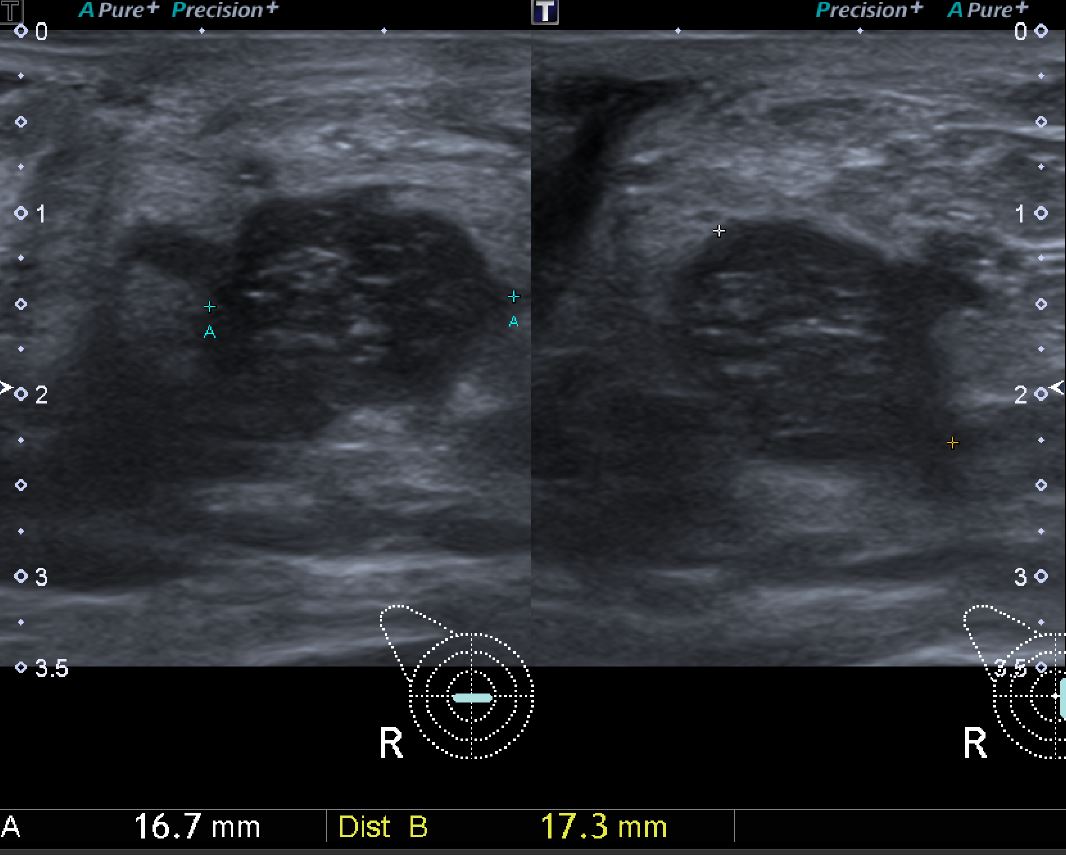

상기환자  60대 여자분으로 건강검진상 이상소견있어 정밀검사위해 내원하시어

오른쪽 젖꼭지 아래부분 조직검사 실시한후 침윤성 유관암 진단되었습니다